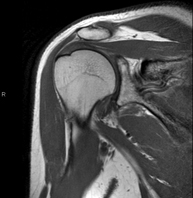

- Shoulder MRI

Examination to study injuries to tendons, muscles and joints. Its main use is to diagnose injuries to the rotator cuff tendons. It lasts approximately 20 minutes. It is a radiation-free procedure.